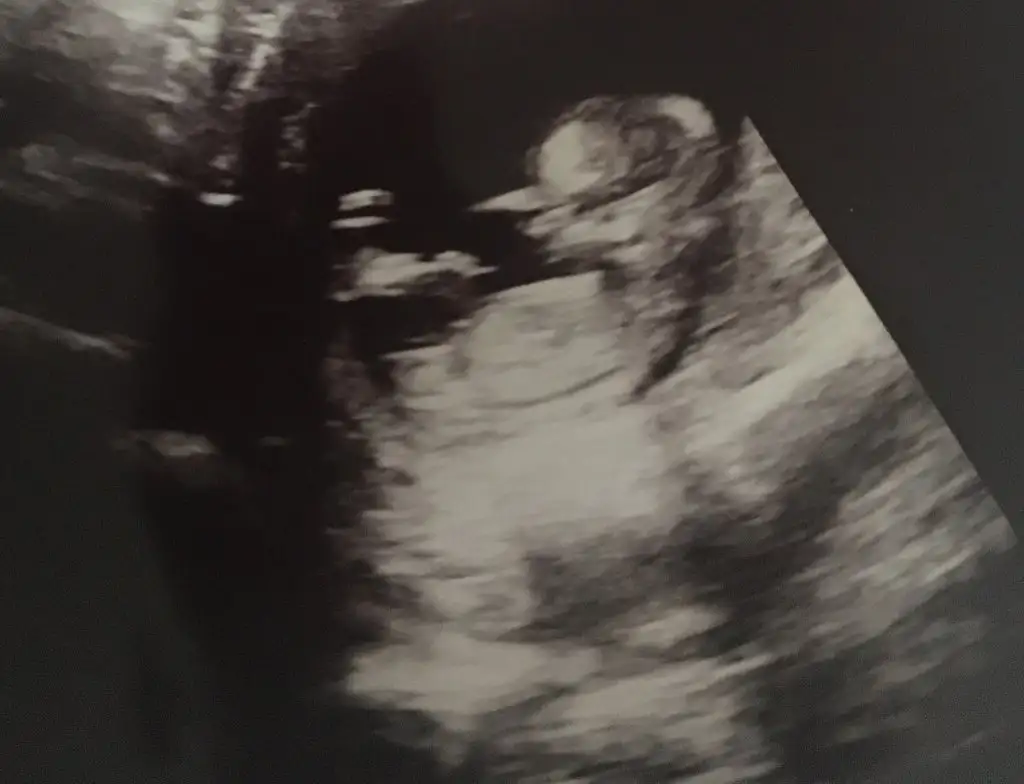

Google den girdim oldu harbiden teşekkürler : ) bakın bakalım benim bebeğimin cinsiyetine bir de bütün fotoğraflarda aynı mı yani kızsa hepsinde kız mı görünüyor erkekse hepsinde erkek mi görünüyor onu söyleyin ben neden hepsinde farklı gördüm acaba.. Ayrıca USG görüntüleri 11 ve 12. Haftalar arasına ait..Yeni üyeyim fotoğraf nasıl yükleniyor acaba yaa bulup da gönderemiyorum yardımcı olur musunuz?? Dosya ekle seçeneğini seçiyorum hiçbir ekran gelmiyor..

Hepsi kız görünüyorGoogle den girdim oldu harbiden teşekkürler : ) bakın bakalım benim bebeğimin cinsiyetine bir de bütün fotoğraflarda aynı mı yani kızsa hepsinde kız mı görünüyor erkekse hepsinde erkek mi görünüyor onu söyleyin ben neden hepsinde farklı gördüm acaba.. Ayrıca USG görüntüleri 11 ve 12. Haftalar arasına ait..

Yaaa gerçekten miiiiii... Ama doktor bana erkek dedi hatta pipisini bile gösterdi.. Bende hep kızım olsun istiyorum acaba kız mı ki yaaa... Şuan 14 haftalığım doktor tam 12 haftalıkken dedi erkek diye...Hepsi kız görünüyor

Ben kız istediğim için doktora emin misiniz belki değişecek ne belli dedim doktor bana güldü evet yanılma payı olabilir 15 16. Haftalar arası en net denilir ama ben sana yine erkek diyeceğim dedi yaaa.. Ama çok acayip istedim ki kızım olsun.. O yüzden belki sizden kız çıkar diye sormak istedim. Teşekkür ederim bakalım ne çıkacakKıza gibi nubu12 hafta cok erken 15-16 olsa doğrudur diyecemde tabi Dr daha detaylı bakar birdaki randevuda netleşir